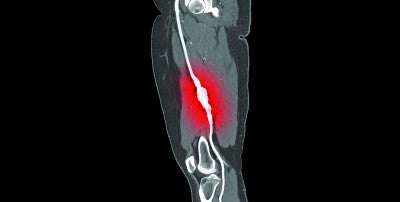

Lower limb amputations are on the rise nationally, a trend related to the aging of the population and the prevalence of diabetes and peripheral arterial disease (PAD). A new multidisciplinary program at Lehigh Valley Heart and Vascular Institute aims to counter this trend by quickly triaging people with limb-threatening conditions to optimum appropriate care.